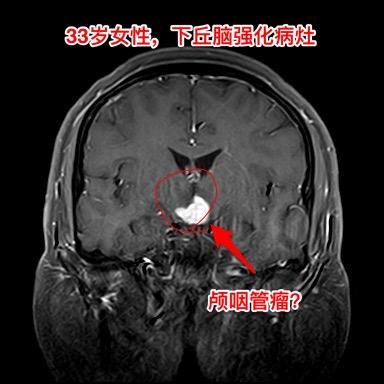

年轻女子四年体重从120斤增到220斤。河北石家庄地区33岁女性,四年前(29岁)开始出现问题,内分泌紊乱(生理周期停了)、多饮多尿,贪食,总爱吃东西,体重稳步增长,四年时间从120斤增长到220斤! 而且还出现多睡,一天到晚躺下就想睡觉。近期还出现记忆力差、头脑糊涂。自从四年前发病后就不能工作了。 2024年12月15日外院的磁共振检查发现下丘脑病变,怀疑是颅咽管瘤。 患者的弟弟找到我,希望我能为他的姐姐解除病痛。 经过仔细分析病人的影像学资